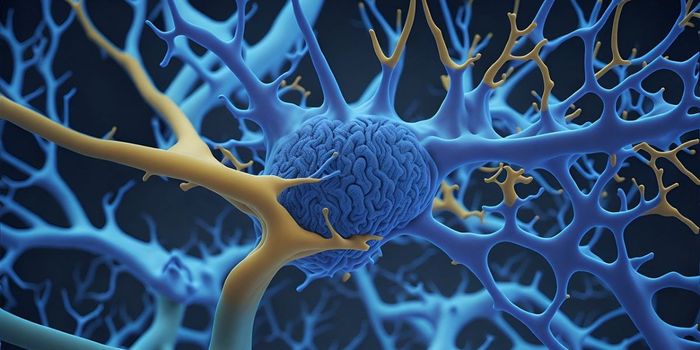

FEB 17, 2025NeuroscienceOver two-thirds of those working after age 50 say that working boosts their physical health, mental health, and overall ...

FEB 17, 2025NeuroscienceResearchers have discovered a new type of neuron that plays a critical role in recognition memory.

FEB 16, 2025NeuroscienceAt least 30 minutes of summer sun per day in the first year of life is linked to a lower relapse risk in children with m ...

FEB 12, 2025Genetics & GenomicsHuntington's disease is a neurodegenerative disorder that is usually fatal about 15 to 20 years after a patient is diagn ...

FEB 11, 2025NeuroscienceA study published in Science Signaling on the neural circuitry mediating addiction has made significant strides, particu ...

FEB 10, 2025NeurosciencePeople with depression tend to prefer carbohydrate-rich foods, according to a new study published in Psychological Medic ...

FEB 09, 2025NeuroscienceShort-term exposure to air pollution reduces people's ability to interpret emotions and focus on performing tasks.

FEB 09, 2025MicrobiologyThe microbes in the human gastrointestinal tract can influence our health and well-being in many ways. The gut-brain axi ...

FEB 09, 2025CancerGlioblastoma (GBM), an aggressive form of cancer that grows in the brain or spinal cord, occurs at an incidence rate of ...

FEB 03, 2025NeuroscienceFrequent social activity may help delay dementia by five years in old age, reported a new study.

FEB 03, 2025NeuroscienceA common mouth and gut bacteria may be linked to a higher risk of stroke, found a new study.

FEB 03, 2025NeuroscienceFlossing teeth at least once per week is linked to a lower risk of stroke and irregular heartbeat beat, known as atrial ...

JAN 26, 2025NeuroscienceOlder adults in the US whose parents divorced when they were children have a 61% higher risk of stroke than counterparts ...

JAN 21, 2025Drug Discovery & DevelopmentDrugs, including antibiotics, antivirals, vaccinations, and anti-inflammatory medications, are linked to a lower risk of ...

JAN 20, 2025NeuroscienceRuminating about being lonely, as opposed to being lonely, is linked to depression, found a new study.

JAN 20, 2025NeuroscienceInhaling xenon gas reduced neuroinflammation and brain atrophy while increasing protective neuronal states in mouse mode ...

JAN 20, 2025Genetics & GenomicsResearchers have made a major breakthrough in our understanding of Huntington's disease. This genetic disorder has long ...

JAN 19, 2025NeuroscienceHigher consumption of red meat is linked to a higher risk of cognitive decline and dementia, reports a new study.

JAN 15, 2025NeuroscienceNatural soundscapes proven to decrease stress, whereas sound pollution was proven to increase stressListening to natural soundscapes has long been associated with feelings of calm and relaxation. Now, a groundbreaking st ...

JAN 14, 2025NeuroscienceA study published in Journal of Neuropsychiatry and Clinical Neuroscience observed the efficacy of donepezil for address ...

JAN 13, 2025NeuroscienceAn AI-powered algorithm could facilitate the diagnosis of a common sleep disorder that affects over 80 million people gl ...

JAN 13, 2025NeuroscienceEarly interventions for depression when symptoms have yet to reach a clinical threshold may reduce depression risk by 42 ...

JAN 12, 2025NeuroscienceMen are over three times as likely than women to die with a traumatic brain injury (TBI), reports a new study published ...

JAN 08, 2025CardiologyCardiovascular risk factors harm the brain in younger people, but the same may not be true in older people.

JAN 06, 2025NeuroscienceChanges to the microbiome from following the Mediterranean diet are linked to better memory and cognitive performance in ...

JAN 06, 2025NeuroscienceSpeaking more than one language is linked with better executive function in children both with and without autism, accor ...

JAN 05, 2025NeuroscienceLoneliness may be linked to a higher risk of heart disease, stroke, and infection susceptibility, suggests a new study.

JAN 01, 2025NeuroscienceA study published in the Journal of the American Medical Association explores the relationship between physical activity ...

JAN 01, 2025Genetics & GenomicsAmyotrophic lateral sclerosis (ALS) is a serious and usually fatal neurodegenerative disorder in which motor neurons det ...

DEC 30, 2024NeuroscienceAtogepant, a recently approved drug for migraine, may start working as soon as day 1 of treatment, according to a recent ...

DEC 30, 2024NeuroscienceA new study found that today's older adults have higher levels of both physical and mental functioning than previous gen ...

DEC 29, 2024NeuroscienceA new study found that most therapies used to treat multiple sclerosis (MS) were linked to a higher risk of low birth we ...

DEC 25, 2024NeuroscienceA study published in The British Medical Journal explored the relationship between occupation and Alzheimer’s dise ...

DEC 24, 2024Drug Discovery & DevelopmentA new compound, called VU319, has delivered promising results in a Phase 1 trial for treating Alzheimer's disease and ot ...

DEC 23, 2024NeuroscienceResearchers found that factors indicative of poor vascular health, such as inflammation and high glucose levels, are lin ...

DEC 23, 2024NeuroscienceA new study found a link between sleep-disordered breathing and larger hippocampal size.

DEC 22, 2024NeuroscienceA new study found that drinking over five cups of caffeinated coffee per day is linked to better cognitive performance i ...

DEC 17, 2024Drug Discovery & DevelopmentA phase 1 clinical trial demonstrated the long-term safety and feasibility of neural stem cell transplantation for treat ...

DEC 16, 2024NeuroscienceA new study found that greater fluctuations in blood pressure readings may be linked to cognitive decline among older Bl ...

DEC 16, 2024NeuroscienceA new study found that socially or mentally stimulating activities like talking to friends, reading, or praying are bene ...

DEC 15, 2024NeuroscienceA new study found that the more readers think AI contributed to a news article, the less they trust its credibility.

DEC 09, 2024NeuroscienceA new study found that a healthy diet can reduce the severity of chronic pain in women.

DEC 09, 2024NeuroscienceIn a new study, large language models (LLMs) predicted neuroscience study outcomes more accurately than human experts.

DEC 08, 2024NeuroscienceA new study found that self-reported loneliness may be more predictive of insomnia than screen time among college studen ...

DEC 05, 2024NeuroscienceA new study found that cannabis affects brain development by interacting with CB1 receptors on astrocytes.

DEC 03, 2024MicrobiologyCompared to other large primates, humans have unusually big brains. Now, scientists have suggested that the large size o ...

DEC 02, 2024NeuroscienceNew research found that enhancing one's appearance- even virtually and in one's own imagination- increases prosocial beh ...

DEC 02, 2024NeuroscienceA new systematic review and meta-analysis investigated the link between alcohol consumption and androgenetic alopecia (A ...

DEC 01, 2024NeuroscienceA new study found that depression may increase the risk of menstrual pain through factors like sleep disturbances.

NOV 25, 2024NeuroscienceA new meta-analysis found that athletes outperform non-athletes in working memory tasks.

NOV 25, 2024NeuroscienceA new study suggests that prenatal immune environments may influence offspring's risk for conditions like Alzheimer's di ...

NOV 24, 2024NeuroscienceA new study found that adolescents who frequently snore are more likely to have behavioral issues like inattention, rule ...

NOV 19, 2024NeuroscienceA study published in the Journal of Affective Disorders proposes a novel, fully automated artificial intelligence (AI) a ...

NOV 18, 2024NeuroscienceA new finger-prick test for Alzheimer's disease has shown similar accuracy to traditional venous blood sampling techniqu ...

NOV 18, 2024NeuroscienceChildren exposed to antiseizure medications while in their mother's wombs may be at a higher risk of developing neurodev ...

NOV 17, 2024NeuroscienceTwo hours per week of class time spent in nature may help reduce emotional distress among 10-12 years olds with signific ...

NOV 12, 2024NeuroscienceSubstance use disorders (SUDs) are a major public health concern, with opioid use disorder (OUD) and alcohol use disorde ...

NOV 11, 2024NeuroscienceA new study found that prolonged mental fatigue can wear down cognitive resources, leading to higher rates of aggressive ...

NOV 11, 2024NeuroscienceResearchers developed an AI algorithm capable of identifying cases of long COVID from electronic health records.

NOV 10, 2024NeuroscienceA new study found that even a single session of vigorous exercise can boost cognitive performance in young adults.